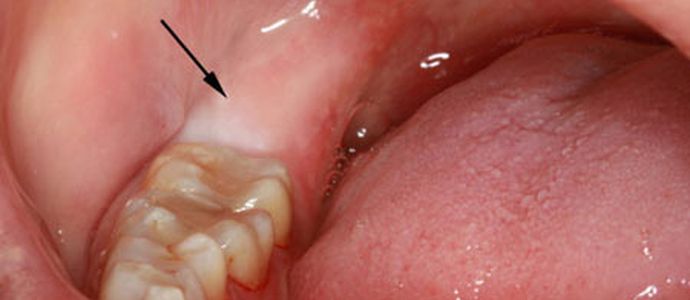

Фото

Слизистая оболочка и мягкие ткани десны над прорезывающимся зубом обычно имеют значительную толщину, что затрудняет выход «восьмерки» и вызывает неприятные ощущения.

- воспалительные процессы – в кармане над проблемным зубом скапливается пища, что может привести к нагноению и пульсирующей боли;

- Травмирование – на верхней челюсти зуб мудрости обычно прорезается в щечную сторону, что вызывает хроническую травму щеки из-за ее прикусывания.

- Язвы – частое зажатие слизистой оболочки между зубами приводит к образованию язв. Эти микротравмы долго не заживают из-за дополнительного травмирующего воздействия при еде и разговоре.